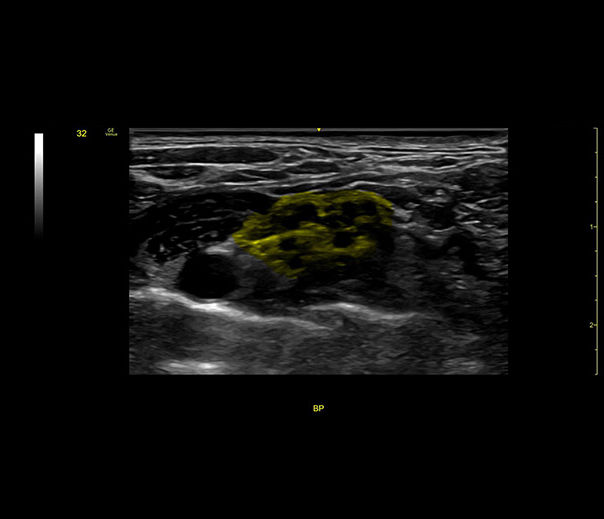

Follow nerve block procedures with cNerve

Helps detect and track nerves in 99% of cases during live scanning or while reviewing a stored clip2 while also displaying a distribution map of the areas on the body impacted by the selected nerve block procedure.